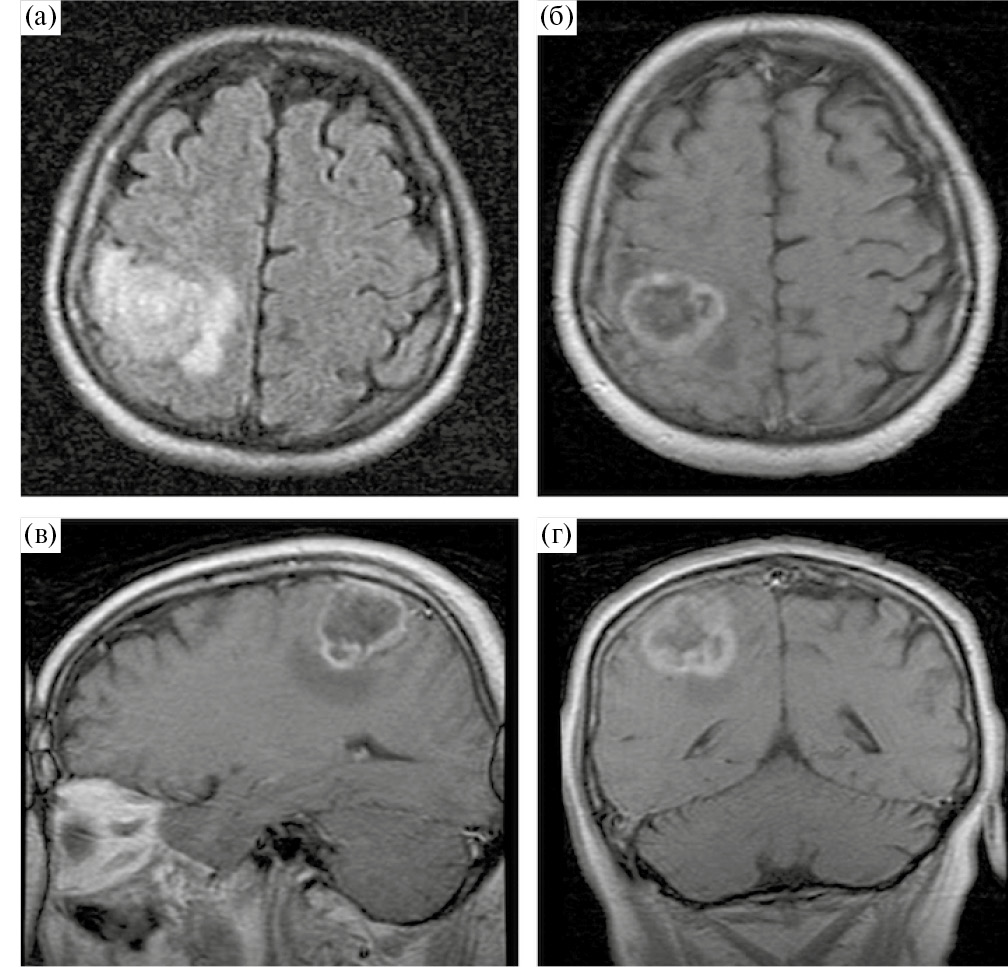

Пациент М., 59 лет, госпитализирован в НМИЦ нейрохирургии им. академика Н. Н. Бурденко с жалобами на слабость, неловкость и онемение в левых конечностях. Данные жалобы возникли около 2 месяцев назад и постепенно нарастали, что послужило поводом для выполнения МРТ головного мозга с в/в контрастированием, которая выявила объемное образование правой теменной доли с умеренным перифокальным отеком, предположительно глиома высокой степени злокачественности, прилежащая к функционально значимым двигательным зонам коры мозга и пирамидного тракта (рис. 3).

Рис. 3. МРТ до операции. Внутримозговая опухоль правой теменной доли, прилегающая к прецентральной извилине. Опухоль кольцевидно накапливает контрастный препарат и окружена небольшой зоной отека-инфильтрации. (а) – аксиальная проекция, Т2-FLAIR, (б) – аксиальная проекция, Т1 + С, (в) – сагиттальная проекция, Т1 + С; (г) – фронтальная проекция, Т1 + С.

Fig. 3. Preoperative MR-images.

При неврологическом осмотре на момент госпитализации у пациента отмечались гипестезия и снижение мышечной силы в левых конечностях до 4 баллов.